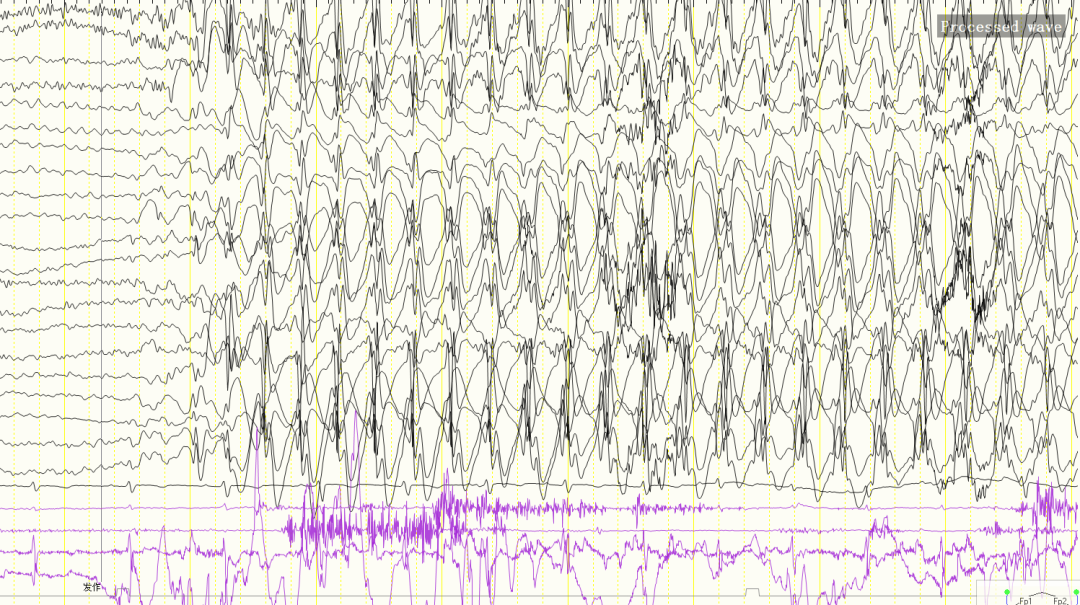

醫(yī)生通過詳細(xì)詢問病史,結(jié)合患兒的年齡、發(fā)作形式、臨床發(fā)作類型等,初步診斷為癲癇中的“失神發(fā)作”。在為患兒進(jìn)行視頻腦電圖監(jiān)測(cè)時(shí),醫(yī)生發(fā)現(xiàn)腦電圖上出現(xiàn)雙側(cè)對(duì)稱同步棘慢復(fù)合波節(jié)律性發(fā)放(異常放電),結(jié)果驗(yàn)證了臨床醫(yī)學(xué)診斷的準(zhǔn)確性,小軍被確診為癲癇的“失神發(fā)作”。